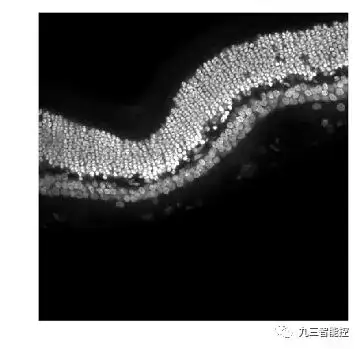

原始图像

(3)视网膜图像